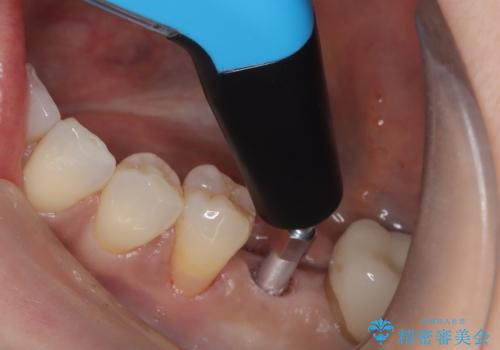

インプラント治療を希望されたため、インプラントを埋入し咬合機能を回復していきます。

骨の量は十分あったため、比較的短期間で治療は終了しました。

安定した咬み合わせとなり、痛みもなく安心して噛めるようになりました。